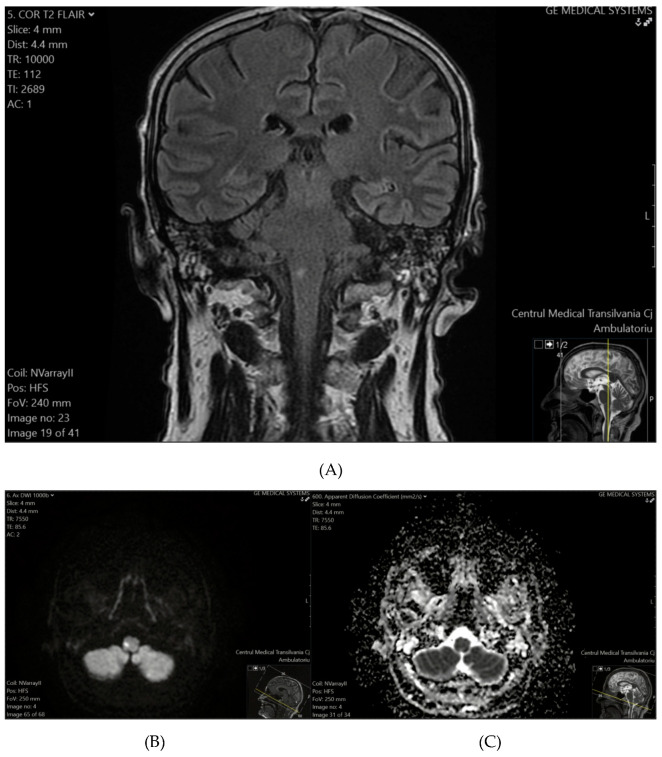

Background: The updated definition of a TIA emphasizes tissue characteristics rather than symptom duration, defining a TIA as a transient neurological episode without ischemic lesions in brain imaging, including in DWI. If imaging reveals a lesion, even in patients with transient symptoms, the event is reclassified as a minor ischemic stroke.

Conclusions: Among the 26 patients clinically diagnosed with TIAs, 7 (26.9%) exhibited ischemic lesions in DWI, reclassifying these cases as minor ischemic strokes under the updated definition. The prevalence of ischemic lesions was notably higher in patients with comorbidities such as hypertension and diabetes. These findings highlight the importance of early MRI-DWI to accurately distinguish TIAs from minor ischemic strokes. Routine urgent DWI within the first week of TIA symptoms enhances diagnosis and risk stratification and can guide targeted stroke prevention strategies, particularly when combined with the ABCD2 score.